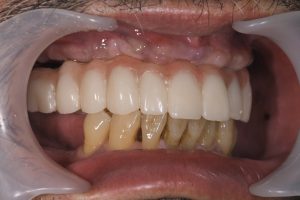

仮歯が装着された状態です。4~6週間は柔らかい食事をとってもらいますが、見かけも良いですし、取り外すこともなく快適に生活できます。

この後、3か月以上経過したら、最終的なジルコニアの歯を製作していきます。